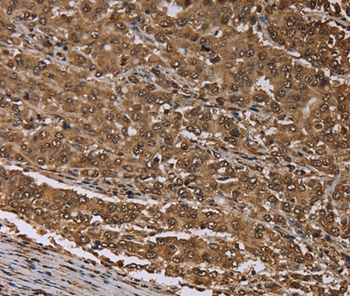

图片:

Immunohistochemical analysis of paraffin-embedded Human liver cancer tissue using #37722 at dilution 1/30.

,

Immunohistochemical analysis of paraffin-embedded Human thyroid cancer tissue using #37722 at dilution 1/30.